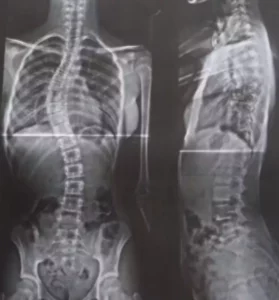

Segundo a mãe, ela já tentou atendimento pelo SUS quatro vezes, mas não encontrou profissionais especializados para o caso. Coluna da menina apresenta uma curva de 52 graus, considerada grave – Foto: Reprodução/acervo pessoal

Sophia Laborda, de 12 anos, foi diagnosticada com escoliose progressiva há dois anos. Desde então, a doença avançou e a curvatura da coluna chegou a 52 graus, um quadro considerado grave. A menina recebeu ajuda de médicos para realizar exames, mas a cirurgia só foi indicada na rede particular.

A doença é considerada rara e de causa desconhecida, surgindo durante a fase de crescimento, a partir dos 10 e 11 anos. Trata-se de uma alteração na coluna vertebral, fazendo com que ela faça uma curva para um dos lados, em formato de “C” ou “S”.

As cirurgias são indicadas quando há progressão que ultrapassa 40-45 graus. Por ser um procedimento invasivo, é meticulosamente programado, com avaliações pré- anestésicas, monitorização neurofisiológica (monitoramento da medula, na qual protege a parte de mobilidade) e dura em torno de duas horas e meia a três horas.